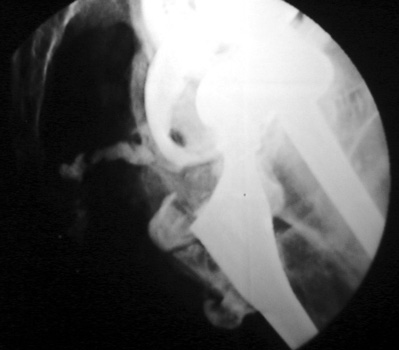

Aspiration of hip after removal of prosthesis. Needle placed

at femoral edge where fluid collects. Needle should not be placed in acetabular

area, which may not be fully intact, risking needle entry into pelvic cavity.